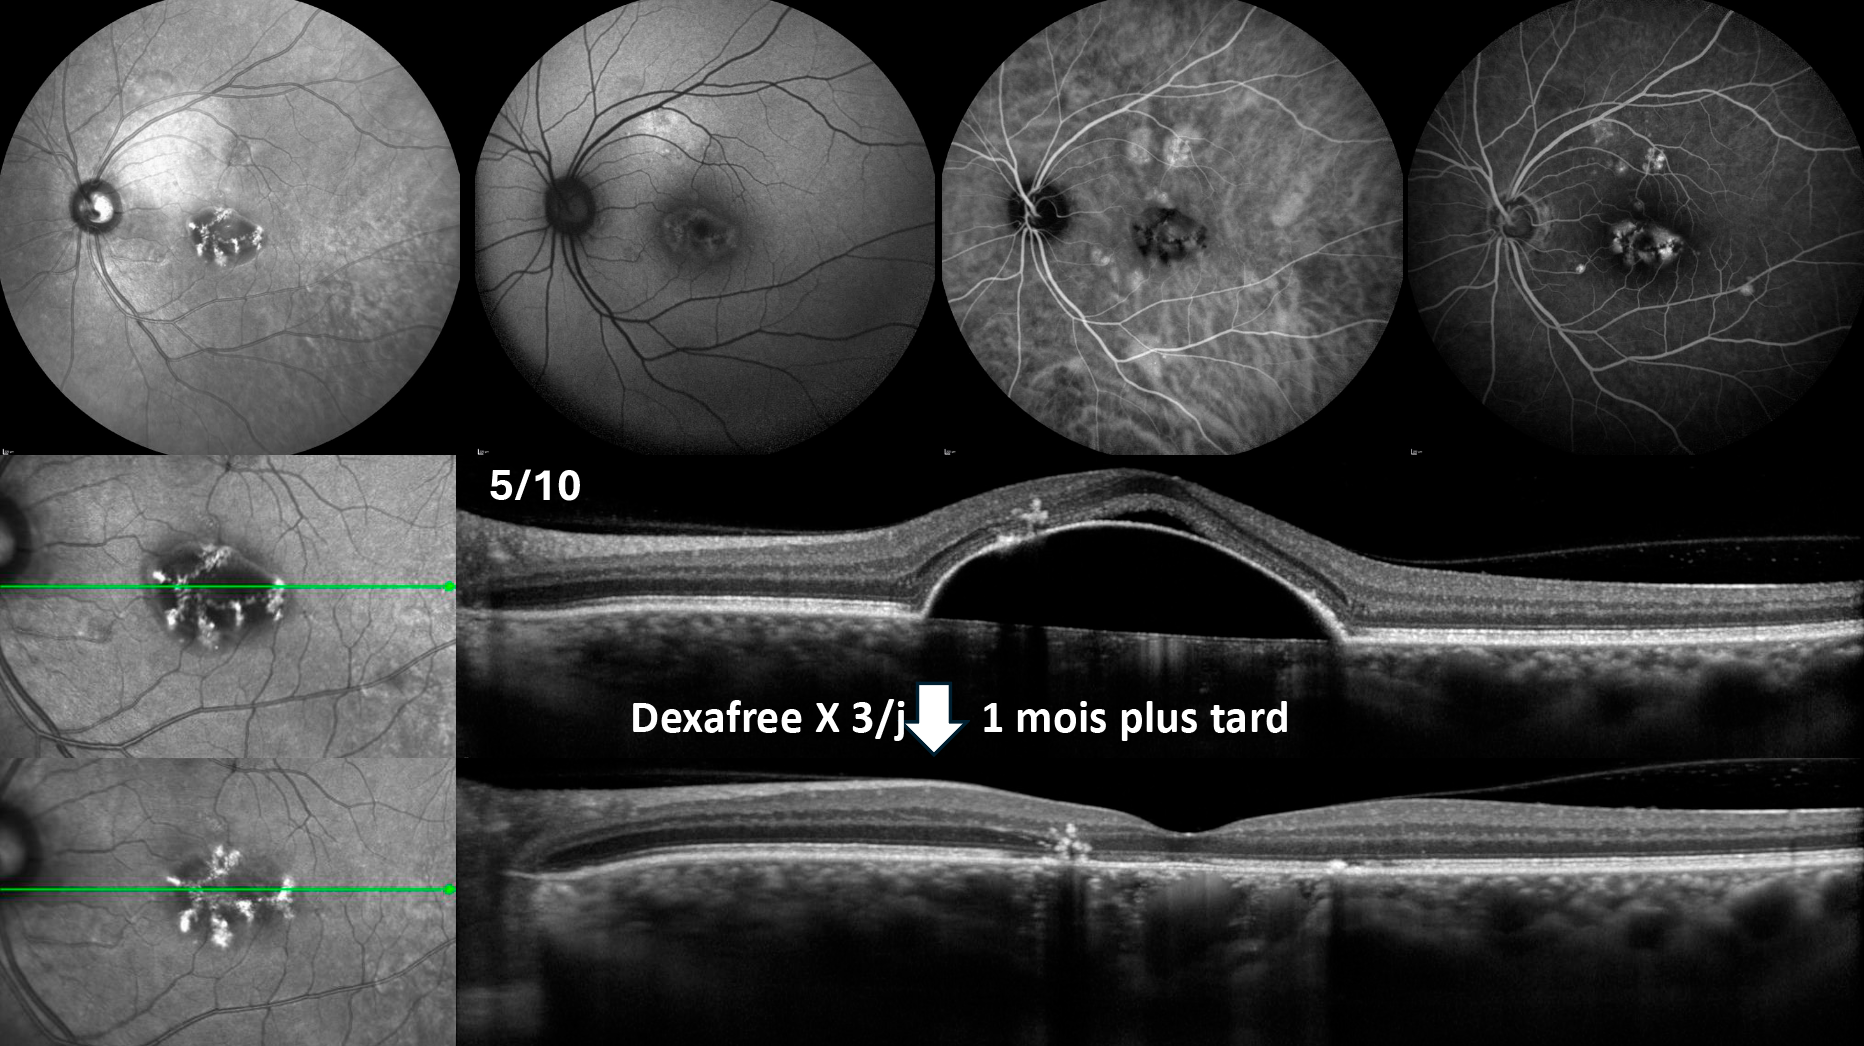

Figure 1. Différents aspects de TelCaps au fond d’œil chez 3 patients diabétiques.

Chez ces 3 patients, les exsudats, de densité variable, sont l’anomalie la plus évidente et témoignent de l’exsudation active, localisée. La télangiectasie capillaire à l’origine de l’exsudation, d’aspect le plus souvent rouge sombre, est souvent peu ou mal visible. Elle doit être recherchée au centre de la couronne d’exsudats.